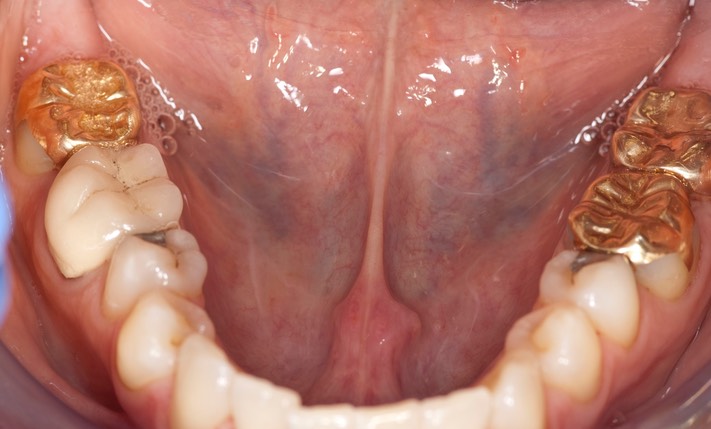

Photos of Clinical Operations

_DSC6212